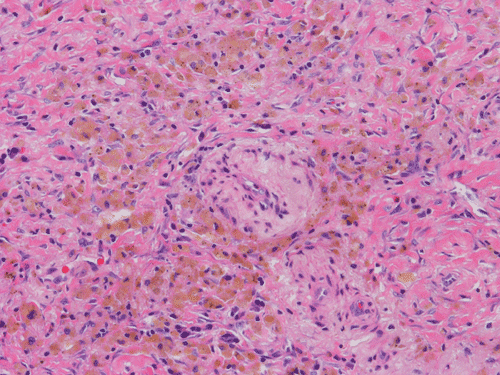

At scanning magnification (Panel A), the lung parenchyma is replaced by some coalescing fibrous nodules. The degree of involvement is variable at different fragments (Panel B and C). In the less affected areas, there are some fibrotic thickening of the septa (Panel C). In some areas, the changes are minimal and the pleural appear to be uninvolved (Panel D and E). In low to medium magnifications, these nodules of fibrosis contains a large number of hemosiderin laden macrophages (Panel F and G) admixed with fibrous tissue. The diagnostic tissue, however, is present in areas with increased cellularity. In these areas, there is a background of cells with a moderate amount of cytoplasm and bland nuclei. Some of these nuclei have kidney shape (arrow in Panel H). In some areas, many of the nuclei have a deep nuclear groove that resemble a coffee bean (arrow in Panel I). In the third type of areas, the nuclear grooving is not distinct (Panel J). Prominent eosinophilic infiltrations are almost always present. Immunohistochemistry on CD1a revealed many positive cells (Panel L). Also present in the specimen are multiple small blood vessels with thickened intima (Panel K). A Movat pentachrome stain demonstrates an internal elastic layer in these vessels and confirms that these are arteries (Panel M and N).

In the end stage, the exhausted lesions are predominantly fibrotic and largely depleted of LCs. In some regions, the fibrosis may surround cystic spaces of variable diameter to form large areas of honeycombing. This is especially predominant in the upper lobes. In cases where parenchymal scaring is present, the pulmonary function will be largely compromised. At this stage, both pulmonary function tests and radiologic findings may suggest diffuse lung disease, but biopsy will show stellate fibrotic lesions centered on the terminal airways with no identifiable interstitial inflammation. Pulmonary vasculopathy (in areas of lung remote from parenchymal nodules) is also seen in late stage PLCH. Vasculopathy manifests as intimal fibrosis, medial hypertrophy or luminal obliteration involving both venules and arteries. This may account for pulmonary hypertension seen late in PLCH.